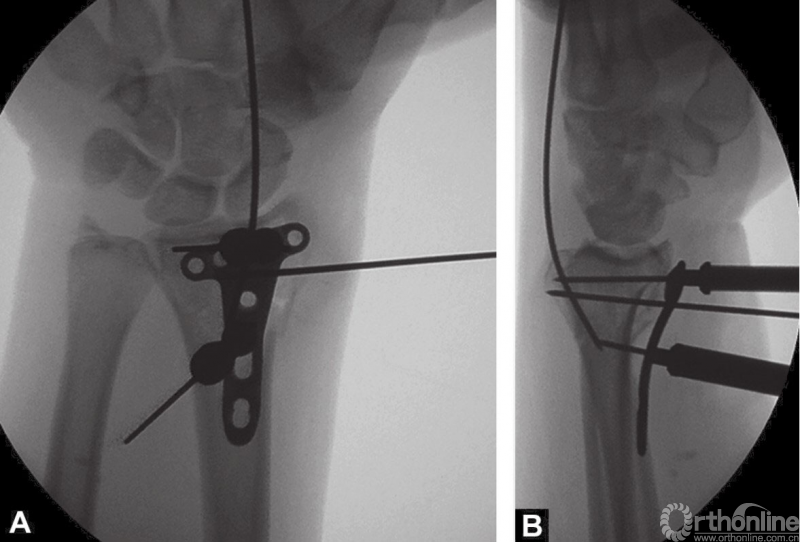

2.4mm桡骨远端T形锁定钢板安放锁定套筒后,置入桡骨远端掌侧面,克氏针通过套筒将钢板临时固定在桡骨远端(图4A和B)。

图4 A和B桡骨远端放置2.4mm锁定钢板和用克氏针临时固定

在软骨下置入远端锁定螺钉能够获得更好的稳定性。X线透视检查钢板放置情况。

远端的锁定螺钉首先置入。接着用一枚普通的2.4mm皮质螺钉置入,将钢板贴向桡骨远端骨面。